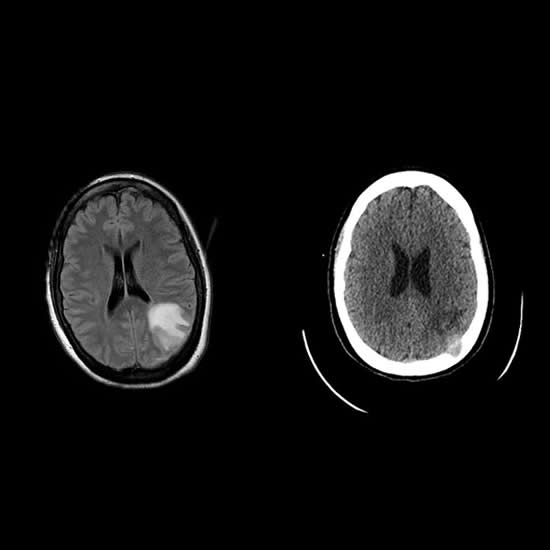

Mujer de 30 años sin antecedentes patológicos ni hábitos tóxicos es derivada del interior de la provincia de Córdoba por Síndrome Convulsivo con antecedente de un TEC en contexto de violencia de género de hace un mes aproximadamente.